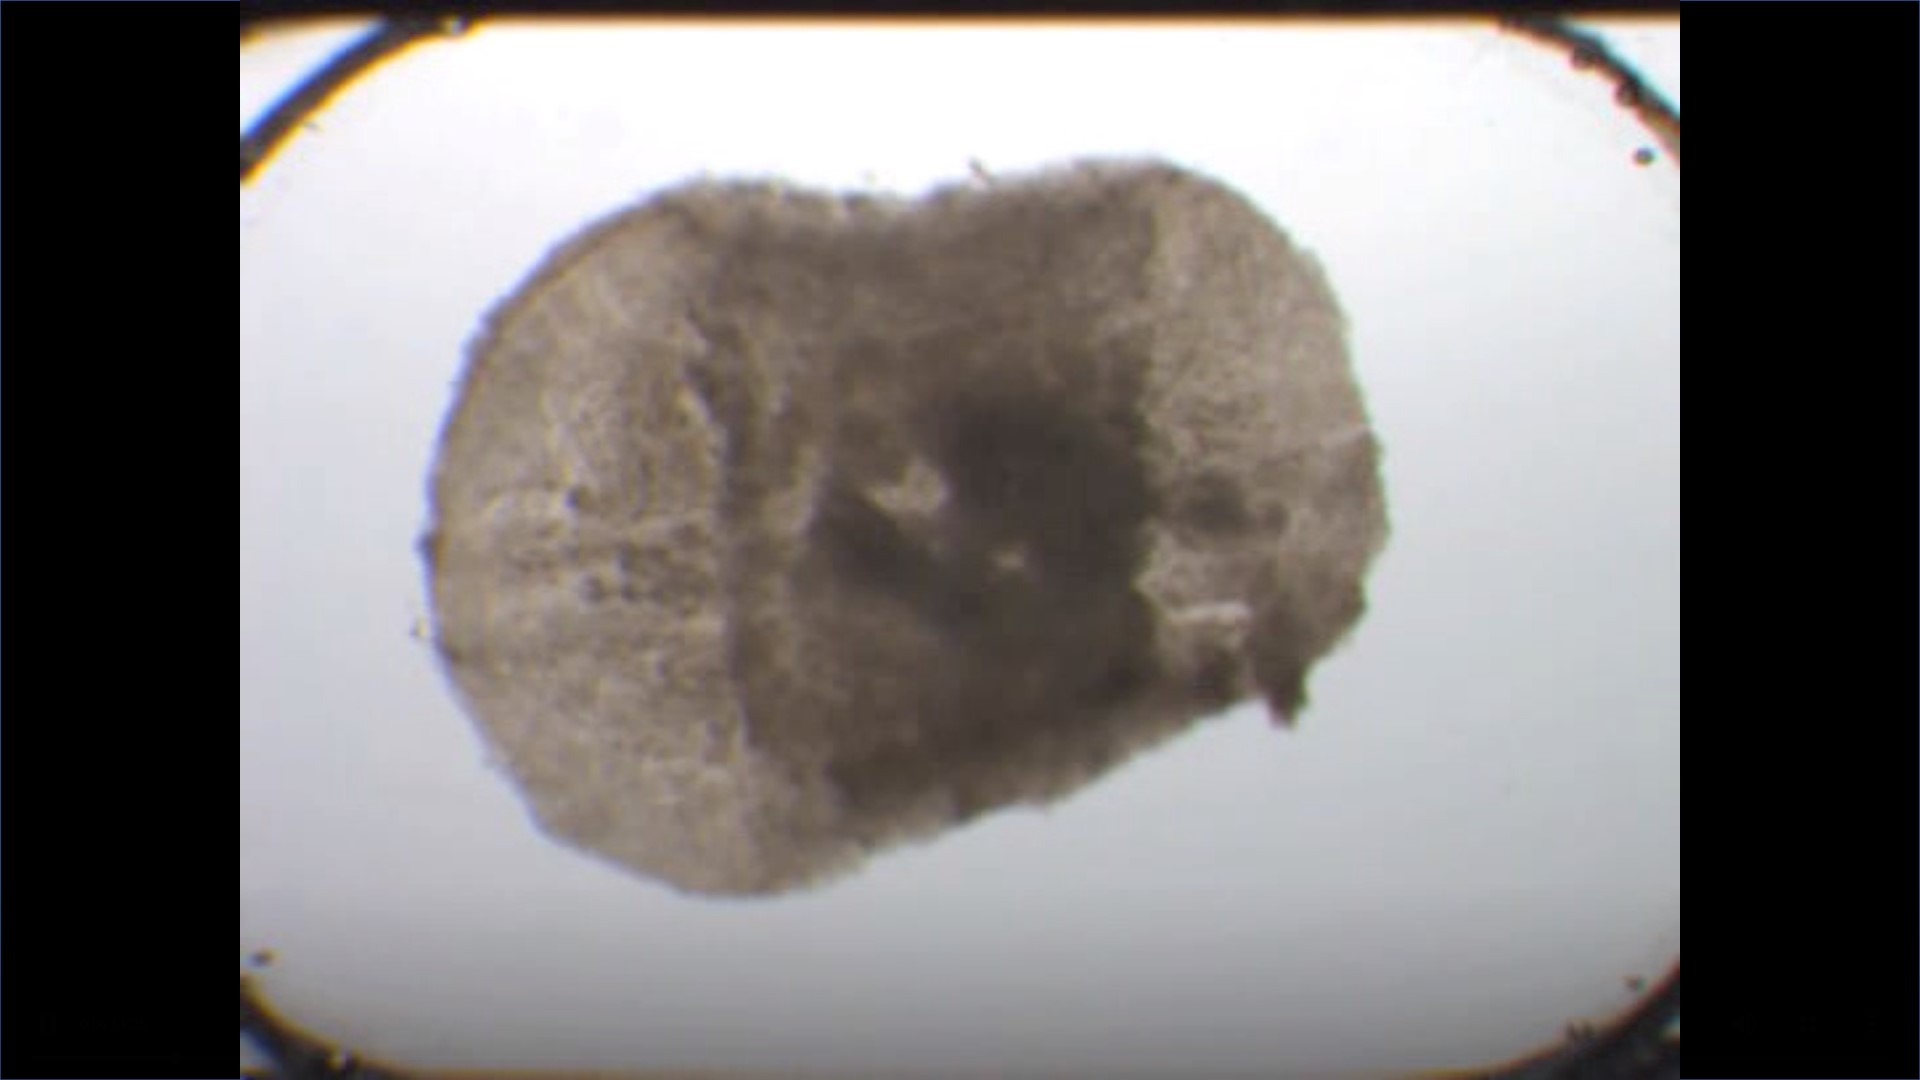

• CIBERONC

El análisis matemático de imágenes tumorales ayuda a entender qué hace que un cáncer pueda ser más o menos agresivo

12/06/2019